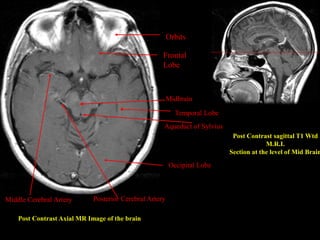

Post Contrast Axial MR Image of the brain

Post Contrast sagittal T1 Wtd

M.R.I.

Section at the level of Mid Brain

Aqueduct of Sylvius

Orbits

Posterior Cerebral ArteryMiddle Cerebral Artery

Midbrain

Frontal

Lobe

Temporal Lobe

Occipital Lobe

Post Contrast AxialMR Image of the brain Post Contrast sagittal T1 Wtd M.R.I. Section at the level of Mid Brain Aqueduct of Sylvius Orbits Posterior Cerebral ArteryMiddle Cerebral Artery Midbrain Frontal Lobe Temporal Lobe Occipital Lobe